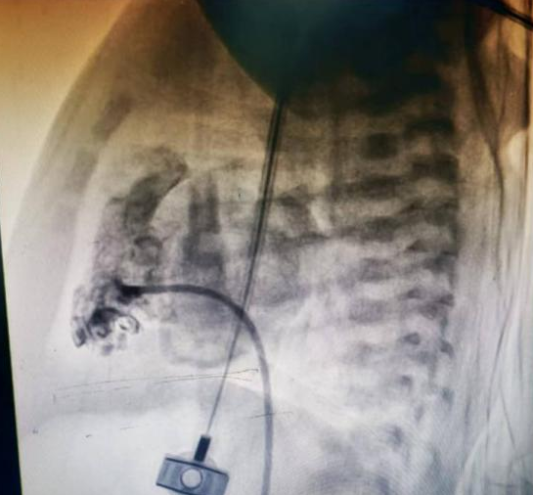

图中为严重狭窄的肺动脉瓣

手术室内,麻醉团队为手术精准护航,新生儿科刘红副主任医师全程严密监护生命体征,守住安全底线。小儿心脏科张庆彪主任团队在影像引导下,凭借高超技术,仅依靠一根微导丝建立轨道,成功将球囊导管送至狭窄的肺动脉瓣处。随着球囊的扩张,原本近乎闭锁的瓣膜被成功打开。术后即时测量显示,跨瓣压差从术前的127mmHg大幅降至12mmHg,患儿血氧饱和度随即显著改善,手术宣告成功。